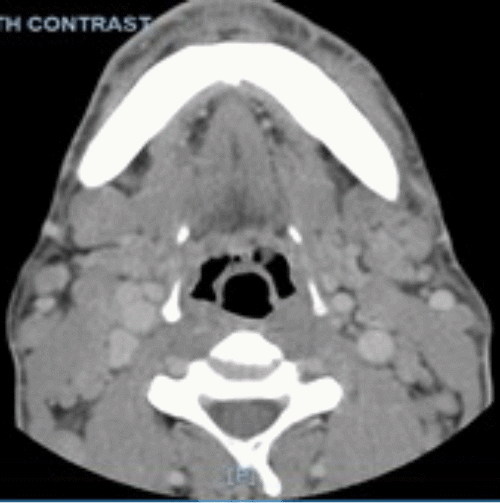

On physical examination, his vitals were within normal limits. He was very thin and had diffuse palpable lymphadenopathy in the cervical and inguinal regions and a large mobile left cheek mass. His abdominal exam was benign, with no anterior abdominal pain but rather bilateral flank pain. The patient's leukocytosis was 13,000 k/cm2, with the remainder of his labs within normal limits; the cluster of differentiation 4 (CD4) count was 2670, and the viral load was 1,391,823. HTLV-I/HTLV-II antibodies were positive. A CT of the abdomen and pelvis with oral and intravenous (IV) contrast was obtained, showing acute tip appendicitis (Figure 1) and extensive bulky gastrohepatic, periportal, peripancreatic, retroperitoneal/para-aortic, bilateral iliac chain, and bilateral inguinal lymphadenopathy (LAD) (Figure 2) with mild splenomegaly suggestive of lymphoma. A CT maxillofacial scan to evaluate his cheek mass also demonstrated extensive bulky cervical lymphadenopathy as well as an enlarged mandibular mass (Figure 3). Of note, the patient had a CT scan performed one year prior that showed an appendix with the same diameter but no local inflammation (Figure 4).

Figure 1. CT Scan: Tip Appendicitis in Pelvis. Published with Permission

Figure 4. CT Scan: Appendix on CT Scan One Year Prior to Presentation. Published with Permission